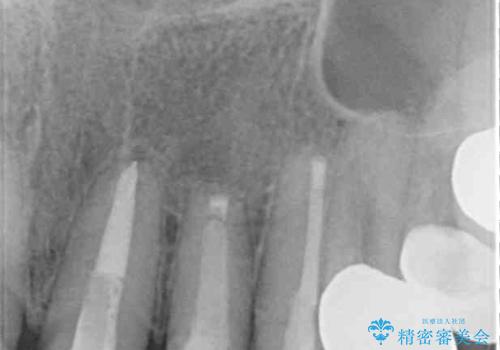

外れてしまったクラウンを保管しておき、新しいクラウン製作の際に技工所に送ることで、今までと同じような色合いに仕上げることができ、周囲のクラウンとバランスを取ることができます。